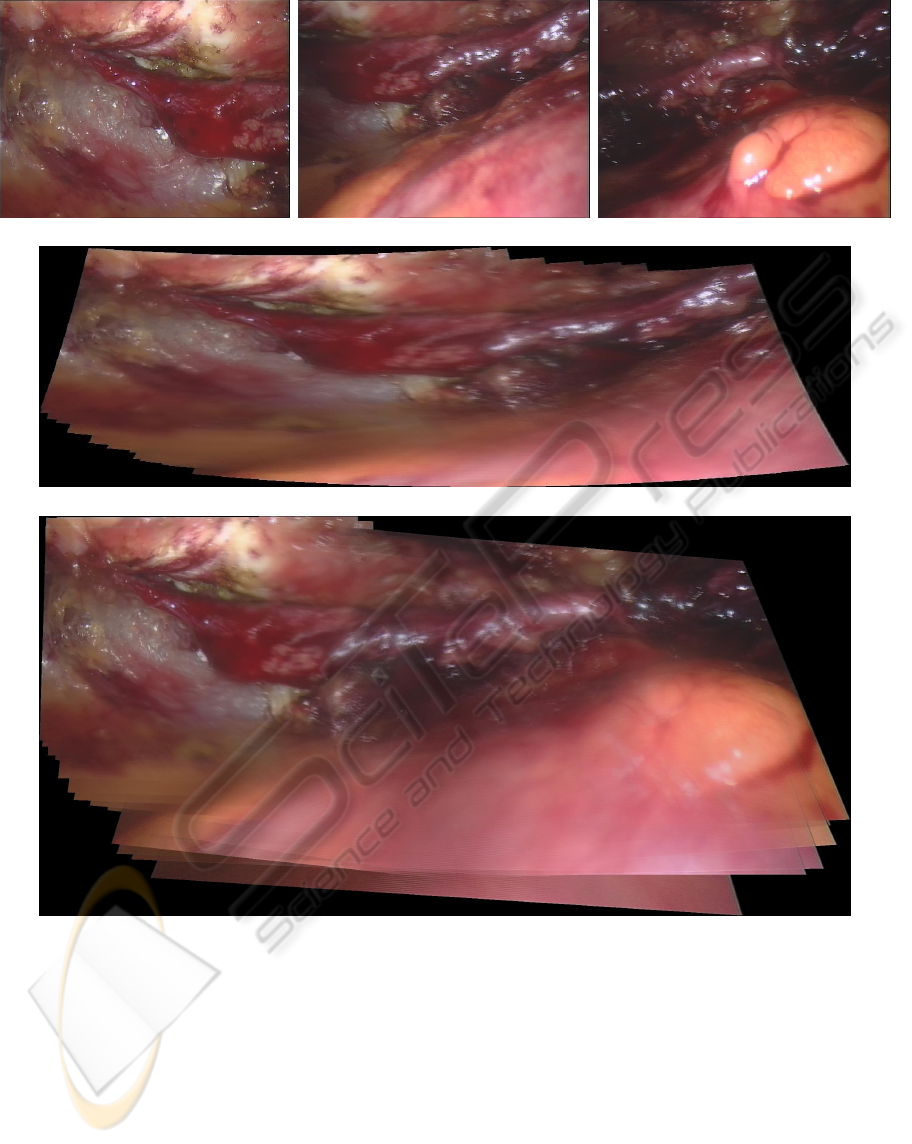

Active Silicon, Uxbridge, U.K.). Although da Vinci

system provides stereo vision, we only use the image

sequence from left camera to perform the mosaicing

in order to compare with other methods. 150 images

were captured from the endoscope but we use only

30 frames (every 5 frame from the sequence) for the

mosaicing. Our aim is to create a mosaicing image

which includes the whole structure of the coronary

artery. The main challenge is the large complicated

non-rigid motion introduced by the beating heart

surface, which is shown in the right bottom of Fig. 2

(b) and (c).

Fig. 2 (d) displays the mosaicing result of the

proposed method. We can notice that the whole

vessel structure has been built correctly. So the

surgeon can realize the environment outside the

current scene when he views a part of the vessel.

More importantly, the mosaicing image can help him

link the endoscopic video with the preoperative

information from CT/MRI scan. Brown’s method

was also tested using this image sequence and the

mosaicing result was displayed in Fig. 2 (e). It is

noticed that only part (around three quarters) of the

whole vessel had been constructed and the images

affected badly by the beating heart surface could not

be used by Brown’s method. The possible reason is

that SIFT feature descriptor could not find enough

reliable features from the images with severe

deformation from the internal organ or soft tissue.